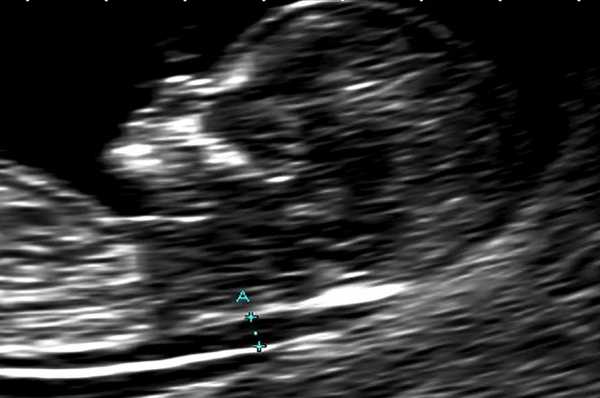

В основной группе численные значения расширенного воротникового пространства плода варьировали от 2,5 до 11,0 мм и превышали соответствующие показатели (5-й, 50-й, 95-й центиль) в группе сравнения в 11-12, 12-13 и 13-14 недель беременности (рис. 1).

Рис. 1. Увеличение толщины воротникового пространства